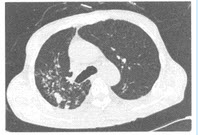

(单选题)本病例痰培养TB菌(+),且其下部层面CT肺窗如图,则图中征象()

A:双轨征

B:春芽征

C:垂柳征

D:印戒征

E:原发复合征